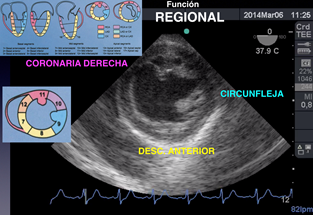

O bien si la causa de la descompensación luego de una reanimación efectiva es isquemia de arteria coronaria izquierda con ETE analizamos los movimientos anormales de la contractilidad regional y por lo tanto reconocemos el territorio isquémico. (Figura e)